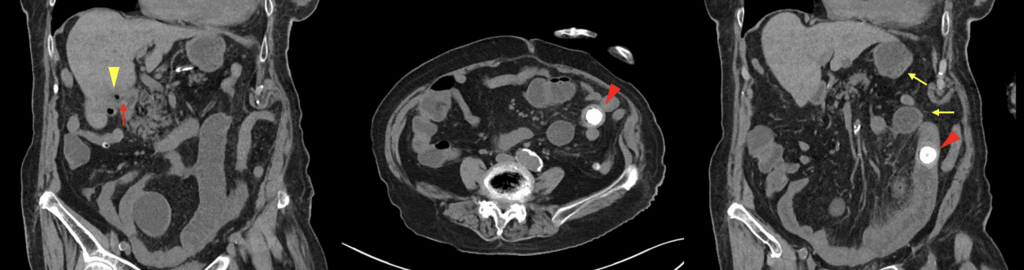

Radiological Examples

Rigler triad: 1. pneumobilia; 2. small bowel obstruction; 3. ectopic calcified gallstone

Case courtesy of Frank Gaillard. Case rID: 6906

2025 – JMA Journal case by Ono and Kitagawa, a 100-year-old woman presented with left flank pain and vomiting. CT imaging confirmed all three components of Rigler’s Triad:

- Pneumobilia

- A 20×30 mm ectopic gallstone in the small bowel

- Evidence of small bowel obstruction

A retrospective CT showed the gallstone had previously been in the gallbladder, confirming passage via a cholecystoduodenal fistula. The patient underwent laparotomy and recovered uneventfully.